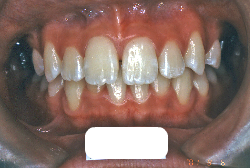

「歯並びの凸凹を直したい」という主訴で来院したケースです。診断の結果、たしかに「叢生」という隙間が足りないと言うことが原因の凸凹症例でした。

しかし、それ以上に問題なのは「前歯の噛み合い方が深すぎる」という症状で、初診の歯の正面写真を見ると下の前歯が全く見えません。こういう症状を矯正学では「過蓋咬合(かがいこうごう)」と言います。過蓋咬合を放置すると、将来的に顎関節に悪影響を与えるとされており、顎関節症の原因因子の一つです。また下の前歯の先端が、上の前歯の裏側の歯茎と強く接触するため、歯周病の原因にもなります。

検査の結果、凸凹が軽症なため非抜歯で矯正すること可能と判断、マルチブラケット装置にて治療しました。治療後は歯並びが綺麗になっただけでなく、噛み合わせ的にも正しい状態が確立しています。